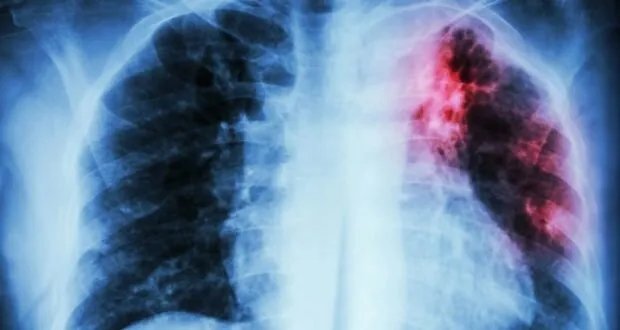

حذرت منظمة الصحة العالمية من أن مرض السل لا يزال يشكل تهديداً عالمياً، مؤكدةً أنه المرض المعدي الأكثر فتكاً في العالم. وكشفت المنظمة في تقريرها السنوي، الذي نقلته وكالة فرانس برس، أن السل تسبب بوفاة حوالي 1.23 مليون شخص خلال العام الماضي.

الجدير بالذكر أن السل مرض يمكن الوقاية منه وعلاجه، وينجم عن بكتيريا تصيب الرئتين في أغلب الأحيان، وينتقل عن طريق الهواء عندما يسعل أو يعطس أو يبصق الأشخاص المصابون.